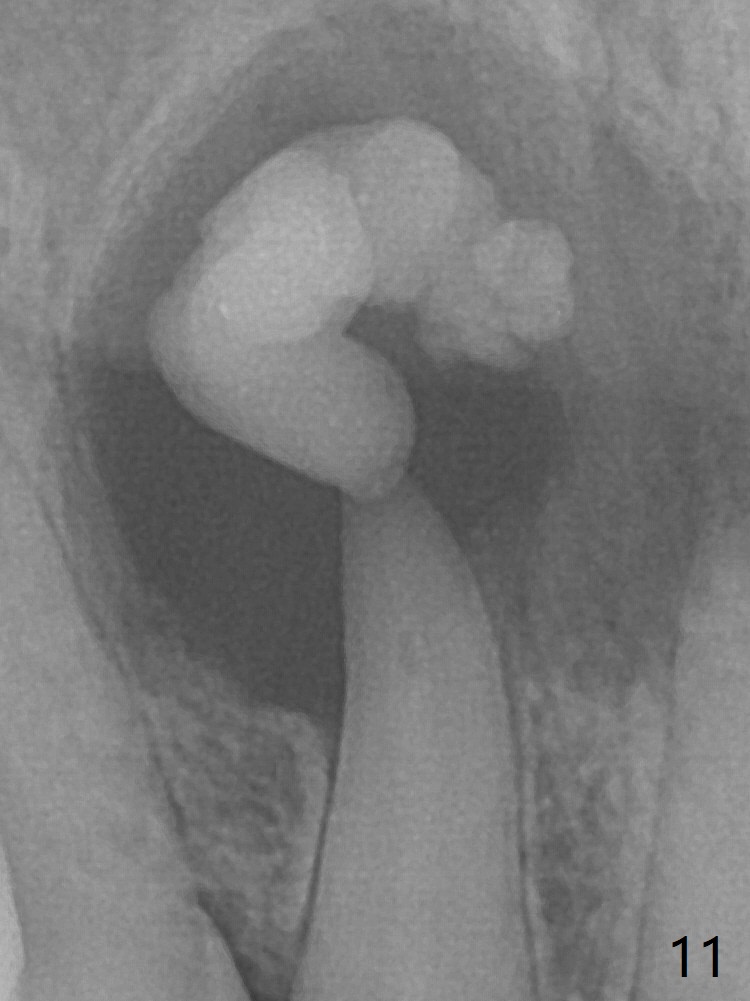

A 47-year-old woman (dental phobic) presented to clinic 9.5 years ago with periapical radiolucency (PARL) at #7 and 9 (Fig.1). RCT was done at #9 because of fistula and symptom 6 months later (Fig.2). While PARL increases at #7 without symptom, that at #9 disappears 8.5 years postop. Three months later, the patient returns for #7 RCT because of the abscesses (Fig.4 *) and pain. Intraop PA is taken with a 30/.06 rotary file in the canal with 19 mm working length (Fig.5). After use of #15 hand file for 20 mm, Ca(OH)2 paste is applied in the canal. When the rubber dam is removed, the abscesses enlarge (Fig.6), which may be related to sodium hypochlorite leakage. A dental explorer is used to try to find a bony opening to the large PARL without success (Fig.7). A postop PA reveals the leakage of Ca(OH)2 paste (Fig.8). Review of the preop PA (Fig.3,9) and intraop PAs (Fig.5,10) shows possible apical resorption and open apical foramen, which is the basis for the paste leakage (Fig.8,11). Careful analysis (with magnification and room light off) of pre- and intra-op PAs should be able to avoid use of #15 hand file out of apical constriction and the complication. The abscess has receded 1 month later (Fig.12). The paste has been resorbed 1 month later (Fig.13). A 30/.06 Gutta Percha is inserted at 18.5 mm (Fig.14 vs. 30/.06 file at 19 mm, 15 file at 20 mm last visit). Fig.15 is the final PA after closure of the access with composite (Fig.15).